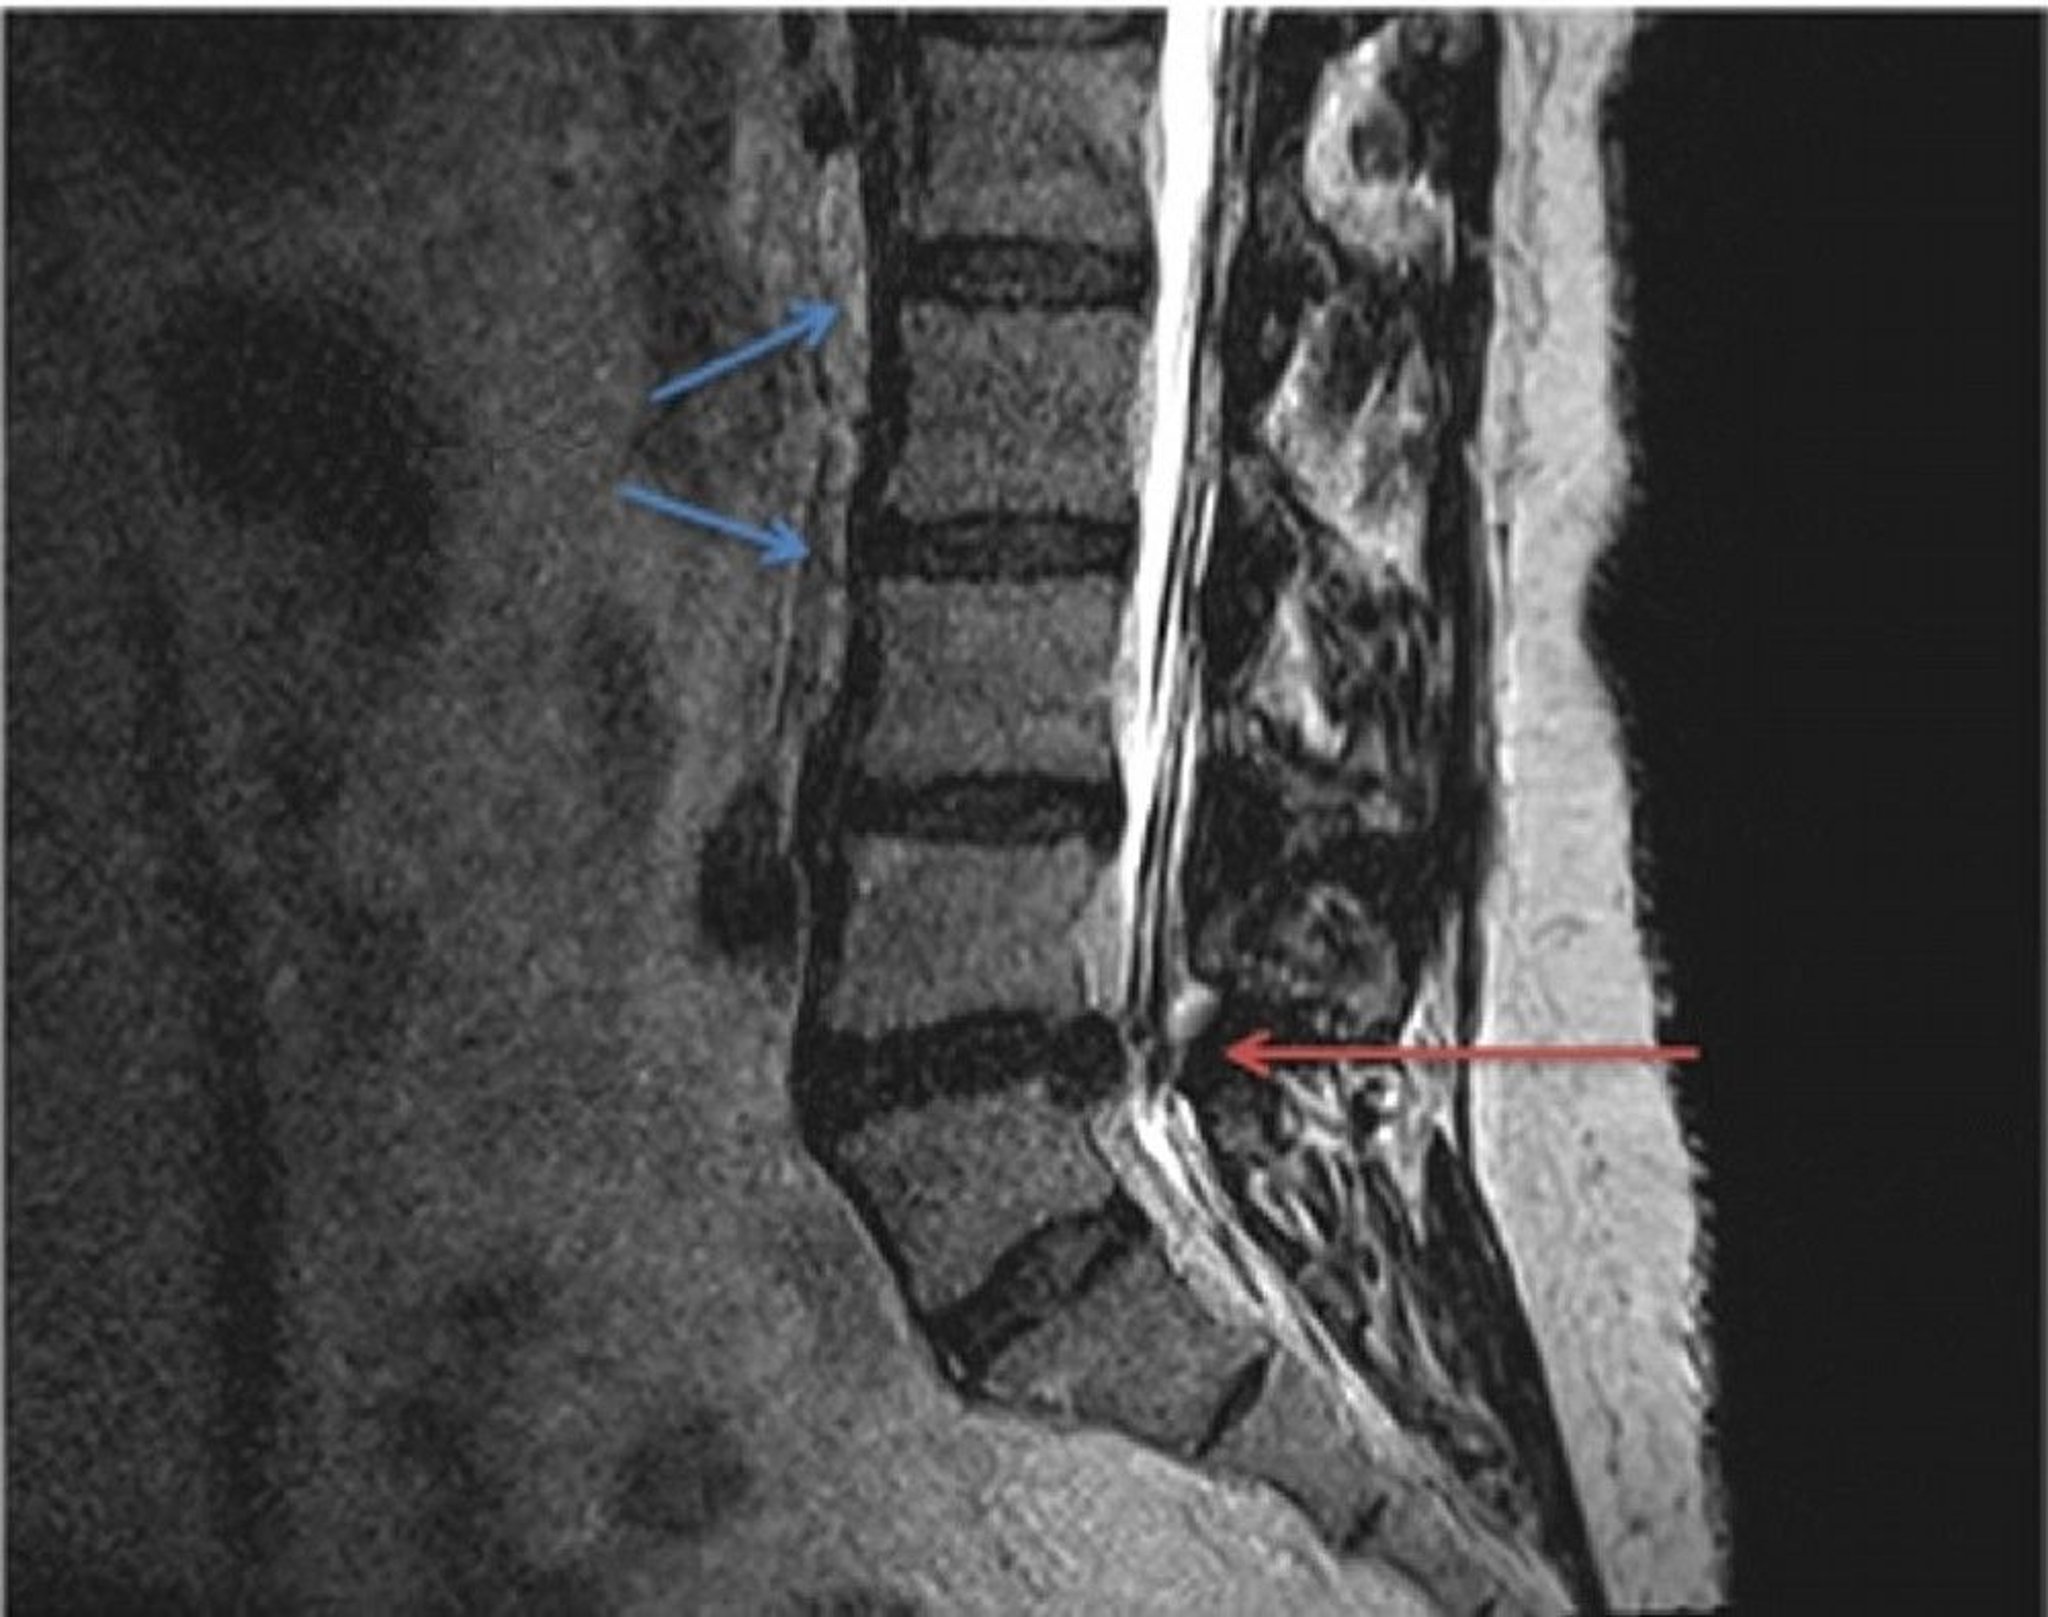

Herniated Disc (MRI Scan)

Comparison of normal (blue arrows) and herniated lumbar disc anatomy in a T2-weighted MRI scan. The herniated disc, located between the L4 and L5 vertebrae (red arrow), is pinching the spinal nerve extending from the spinal cord, resulting in localized or radiating pressure and pain.